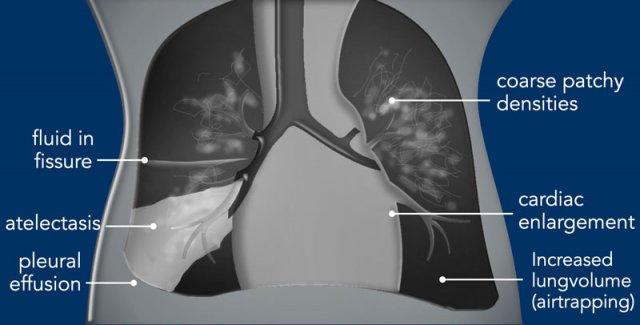

Imaging

- Increased lung

volume due to air trapping. - Bronchiolitis

can lead to atelectasis and air trapping. - Tắc nghẽn hoàn toàn phế quản có thể dẫn đến xẹp phổi.

- Đục mờ thô, lan tỏa hai bên dạng đốm hoặc dạng tuyến tính hơn.

- Can present

asymmetrical. - Pleural

effusions can be seen. - Ở giai đoạn muộn hơn, tăng áp phổi dai dẳng biểu hiện là tim to trên phim X-quang.